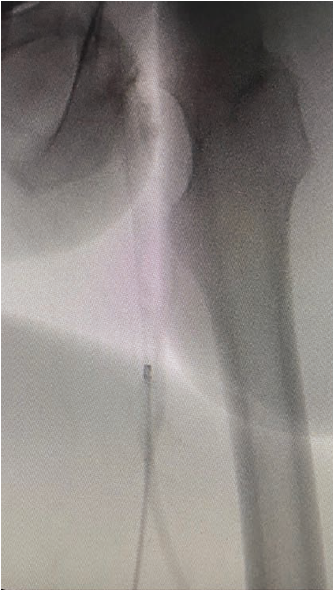

In the DVT space, one of the nice aspects of the Aspirex™ Mechanical Aspiration Thrombectomy System is that you can attach a pressurized bag mixed with contrast and heparinized saline, and infuse contrast as you are performing your thrombectomy. By virtue of its size, the catheter is close to being occlusive to a fistula or graft, so I don’t use the contrast bag in the dialysis space. For DVT treatment, the contrast allows you to see what clot remains and direct your catheter towards those areas. I have found this ability to infuse contrast exceptionally valuable. I understand physicians are concerned about giving extra contrast in procedures, but in my experience, what makes the Aspirex™ Mechanical Aspiration Thrombectomy System unique is its strong aspiration, which can remove the contrast after it does its job in staining the residual clot. My goal is to stain the residual clot with contrast for better visibility under fluoroscopy. Use a longer sheath instead of a short sheath, keep your sheath tip close to the tip of the catheter, continuously infuse, and visualize any areas of clot that remain.

The learning curve with the Aspirex™ Mechanical Aspiration Thrombectomy System requires understanding how to rely on wire bias to manipulate and deflect the tip of the catheter from wall to wall as you are performing the thrombectomy, which allows you to realize the full debulking potential of the device, rather than remaining in the center line in the middle of the vein. After learning the wire bias technique, you can watch on venography as the tip of the catheter deflects from wall to wall and your thrombectomy success dramatically improves.

For radiocephalic fistulas, brachiocephalic fistulas, brachiobasilic fistulas, and brachial-axillary grafts, using a radial access works wonders. There is plenty of literature showing that a transradial approach to intravascular intervention is safe and effective. Prior to the procedure, I do a modified Allen’s test. I will put an O2 sensor on the patient’s finger and occlude the radial artery to make sure that the oxygen remains at an acceptable level. If it does, I proceed with the idea that the ulnar artery and palmar arch are patent and complete. Under ultrasound guidance, I access the radial artery using a micropuncture kit. I would probably shy away from using radial access when there is circumferential calcification of the radial artery, but we don’t see that very often, or a very diminutive radial artery — one that feels good on pulse exam, but looks really, really small on ultrasound. But probably in about 97-98% of my cases, I am sticking the radial artery. I give 2.5 mg of verapamil and 2000 IU of heparin, and flush the catheter and the sheath with heparinized saline. I use a 6F Glidesheath Slender® Hydrophilic Coated Introducer Sheath (Terumo Interventional Systems), take my initial arteriogram, venogram, or fistulogram, then redirect the wire from the radial artery into the fistula. If it is radiocephalic, typically you don’t need a catheter. If it’s brachiocephalic, brachiobasilic, or an AV graft, it would be up the arm, but sometimes you do need a selective catheter to get in, especially if there is any perianastomotic stenosis. After I perform balloon angioplasty or thrombectomy, what I want to see is brisk flow from the artery into the fistula itself. I don’t want to see any more filling of the artery proximal to the fistula. If the artery is filling proximal to the fistula, then there is still something there, either clot in the arterial plug, clot in the outflow vein or graft, or some stenosis that I haven’t yet recognized. The nice part about radial access, as I previously mentioned, is with the ability to treat in one direction, you can access in flow such as in the artery distal to the anastomosis in an antegrade fashion, or beyond the clot in the vein and go retrograde, when treating in the AV circuit. The Aspirex™ Mechanical Aspiration Thrombectomy System has an atraumatic catheter design, so I start performing the thrombectomy just distal to the anastomosis. That way I know that I am starting where there is sufficient blood flow, which is necessary with this particular catheter. I slowly advance retrograde to the arterial plug and then use a slow, back-and-forth motion throughout the entire outflow in an antegrade fashion, which is the indicated catheter movement for the Aspirex™ Mechanical Aspiration Thrombectomy System. I then take another fistulogram and continue to perform fluoroscopic-directed catheter thrombectomy where needed.